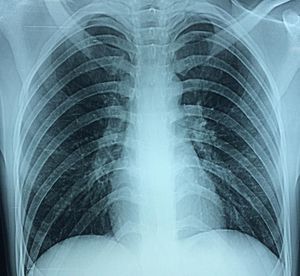

What seems to be the problem on this CXR ?